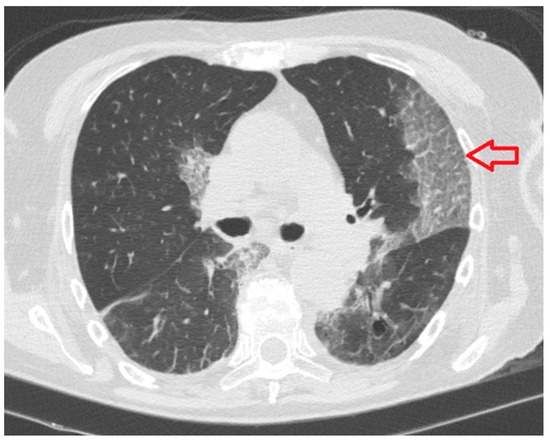

- Crazy paving pattern: thickened interlobular septa and intralobular lines superimposed on a background of ground glass opacity (Figure 5);